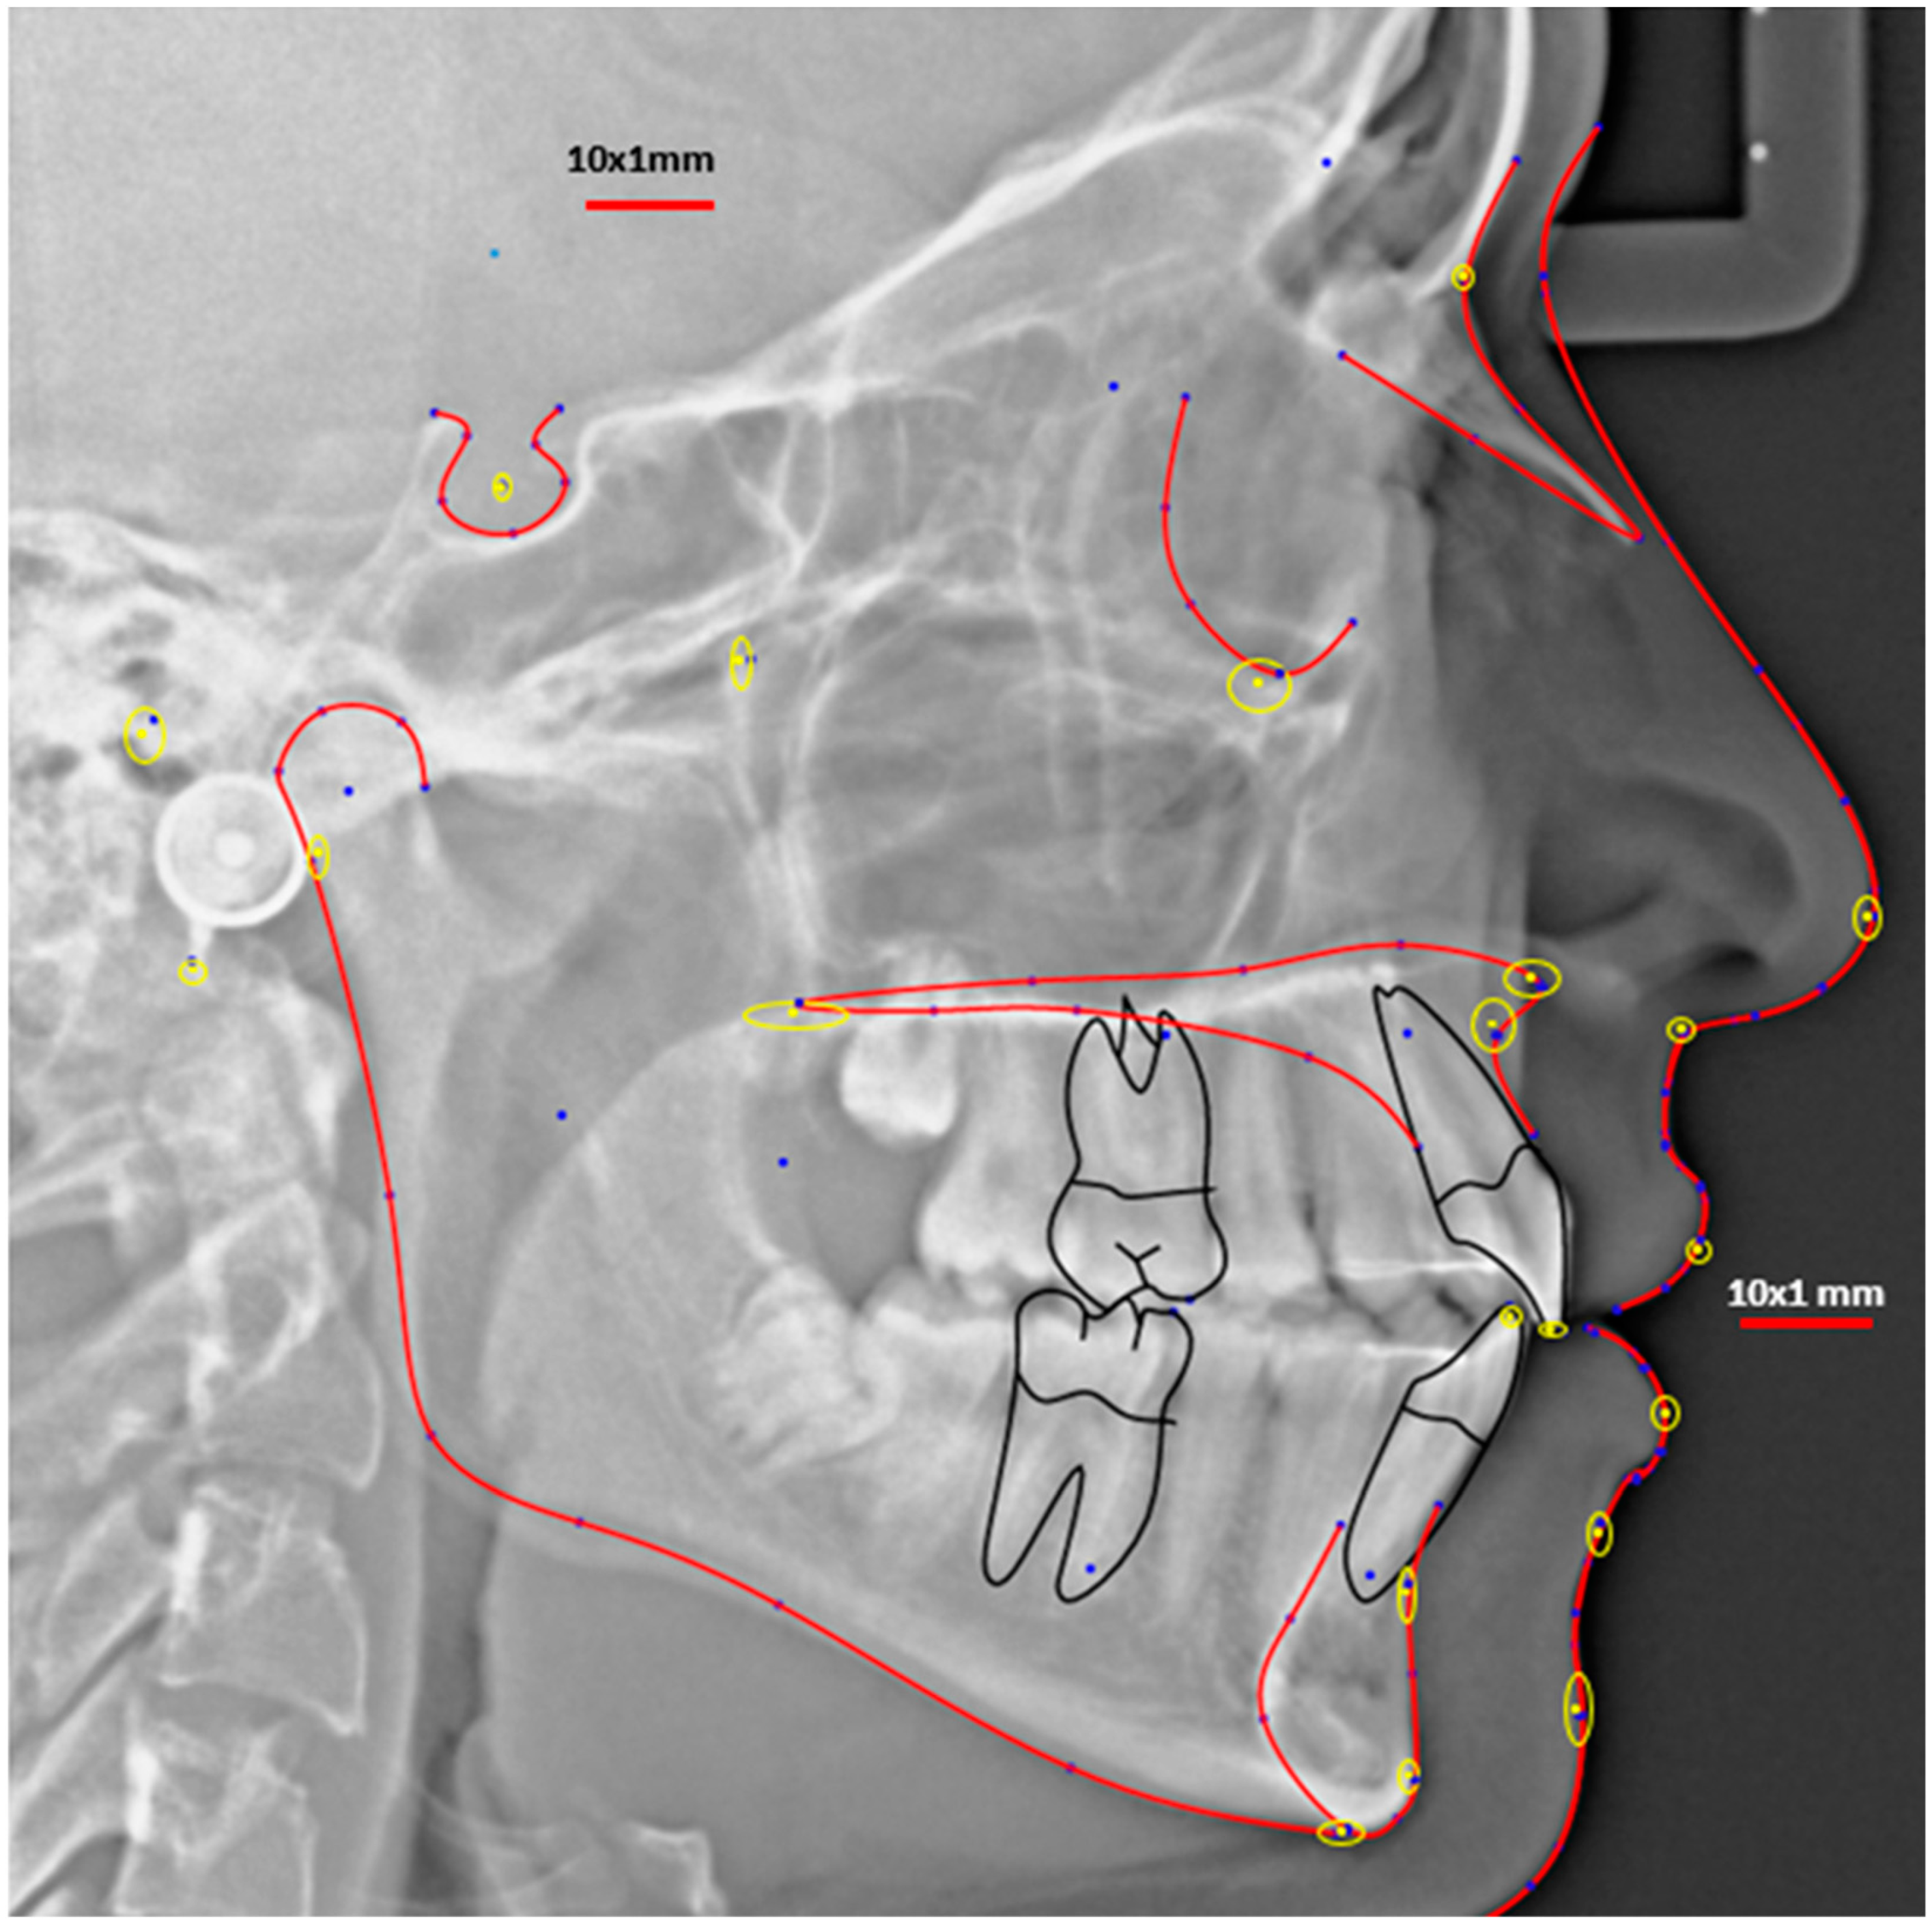

| Landmark | Definition | |

|---|---|---|

| 1 | Sella | Midpoint of sella turcica |

| 2 | Nasion | Most anterior point on frontonasal suture |

| 3 | Upper incisor tip (UI) | Tip of most prominent upper central incisor |

| 4 | Lower incisor tip (LI) | Tip of most prominent lower central incisor |

| 5 | B point | Deepest bony point on mandibular symphysis between pogonion and infradentale |

| 6 | Pogonion (Pog) | Most anterior point of mandibular symphysis |

| 7 | Menton | Lowest point on mandibular symphysis |

| 8 | Articulare | Junction between inferior surface of the cranial base and the posterior border of the ascending ramus of the mandible |

| 9 | A point | deepest point of premaxilla concavity bellow ANS |

| 10 | ANS | Tip of anterior nasal spine |

| 11 | PNS | Posterior limit of bony palate |

| 12 | Soft pogonion (Softpog) | Most anterior soft tissue point of soft chin |

| 13 | Soft B | The deepest soft tissue point between chin and subnasale |

| 14 | Lower lip | The most anterior point of lower lip |

| 15 | Upper lip | The most anterior point of upper lip |

| 16 | Subnasale | The junction where base of the columella of the nose meets the upper lip |

| 17 | Softnose | Most anterior point of nose tip |

| 18 | Orbitale | Most inferior point on the orbital margin |

| 19 | PTM | The intersection of the inferior border of the foramen rotundum with the posterior wall of the pterygomaxillary fissure |

| 20 | Porion | Most superior point of outline of external auditory meatus |

| 21 | Basale | The most inferior point on the anterior border of the foramen magnum in the midsagittal plane |